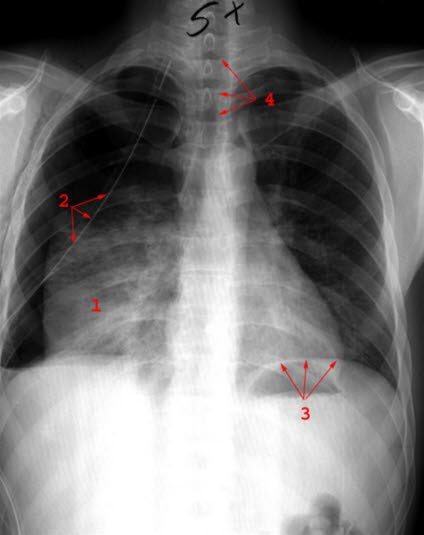

Lobærpneumoni

Fortetning i underlappen høyre side

1. Fortetning

2. Kateter

3. Luft i magesekken

4. Trachea